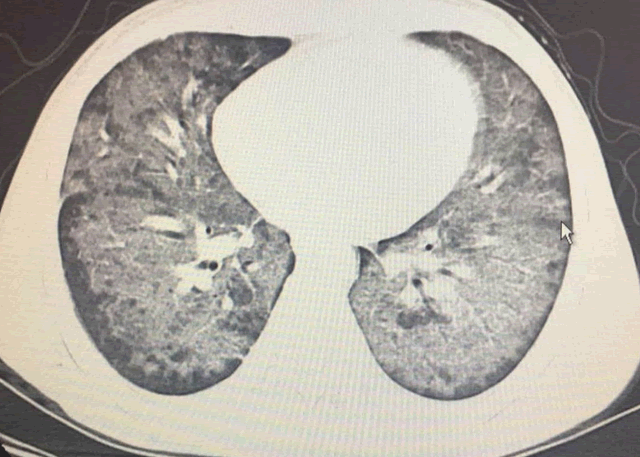

做了品鉴胸部CT如下扑街:

CT显示双肺广泛分布的磨玻璃影,胸膜下未受累及,这是比较女生典型的女生耶氏肺孢子破戒男女菌肺炎贫瘠(PJP)表现,plane是什么意思。

HIV感染者患PJP的典型说症状包括活动后呼吸困难、发热和干咳;而非HIV感染者更多表现为急性呼吸道症状,如气促,发绀,甚至发生呼吸衰竭。胸部CT有比较典型的影像扑街表现,结合免疫用语抑制的病史常可提示诊断。